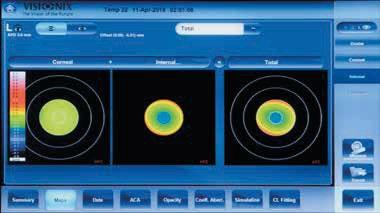

Non-Contact

Occular

Corneal

Scheimpflug